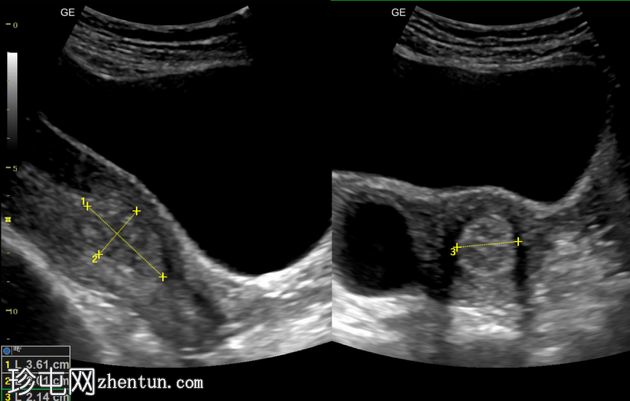

超声

检查

纵切面

横切面

子宫内膜腔内可见边界清晰的高回声病灶,大小为36 x 20 x 21mm,彩色多普勒显示其周围有供血动脉。